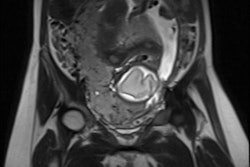

The researchers plan to use the Toshiba scanner and its Superb Micro-Vascular Imaging (SMI) and shear-wave elastography techniques to predict which women might have poor pregnancy outcomes by analyzing microvascularization of the placenta, placental tissue elasticity, and placental calcification content. The goal is to ultimately develop an algorithm that can predict late pregnancy complications in early gestation.

The study is part of the Human Placenta Project, which is a research initiative by the Eunice Kennedy Shriver National Institute of Child Health and Human Development. NIH has awarded 19 grants, totaling approximately $46 million.